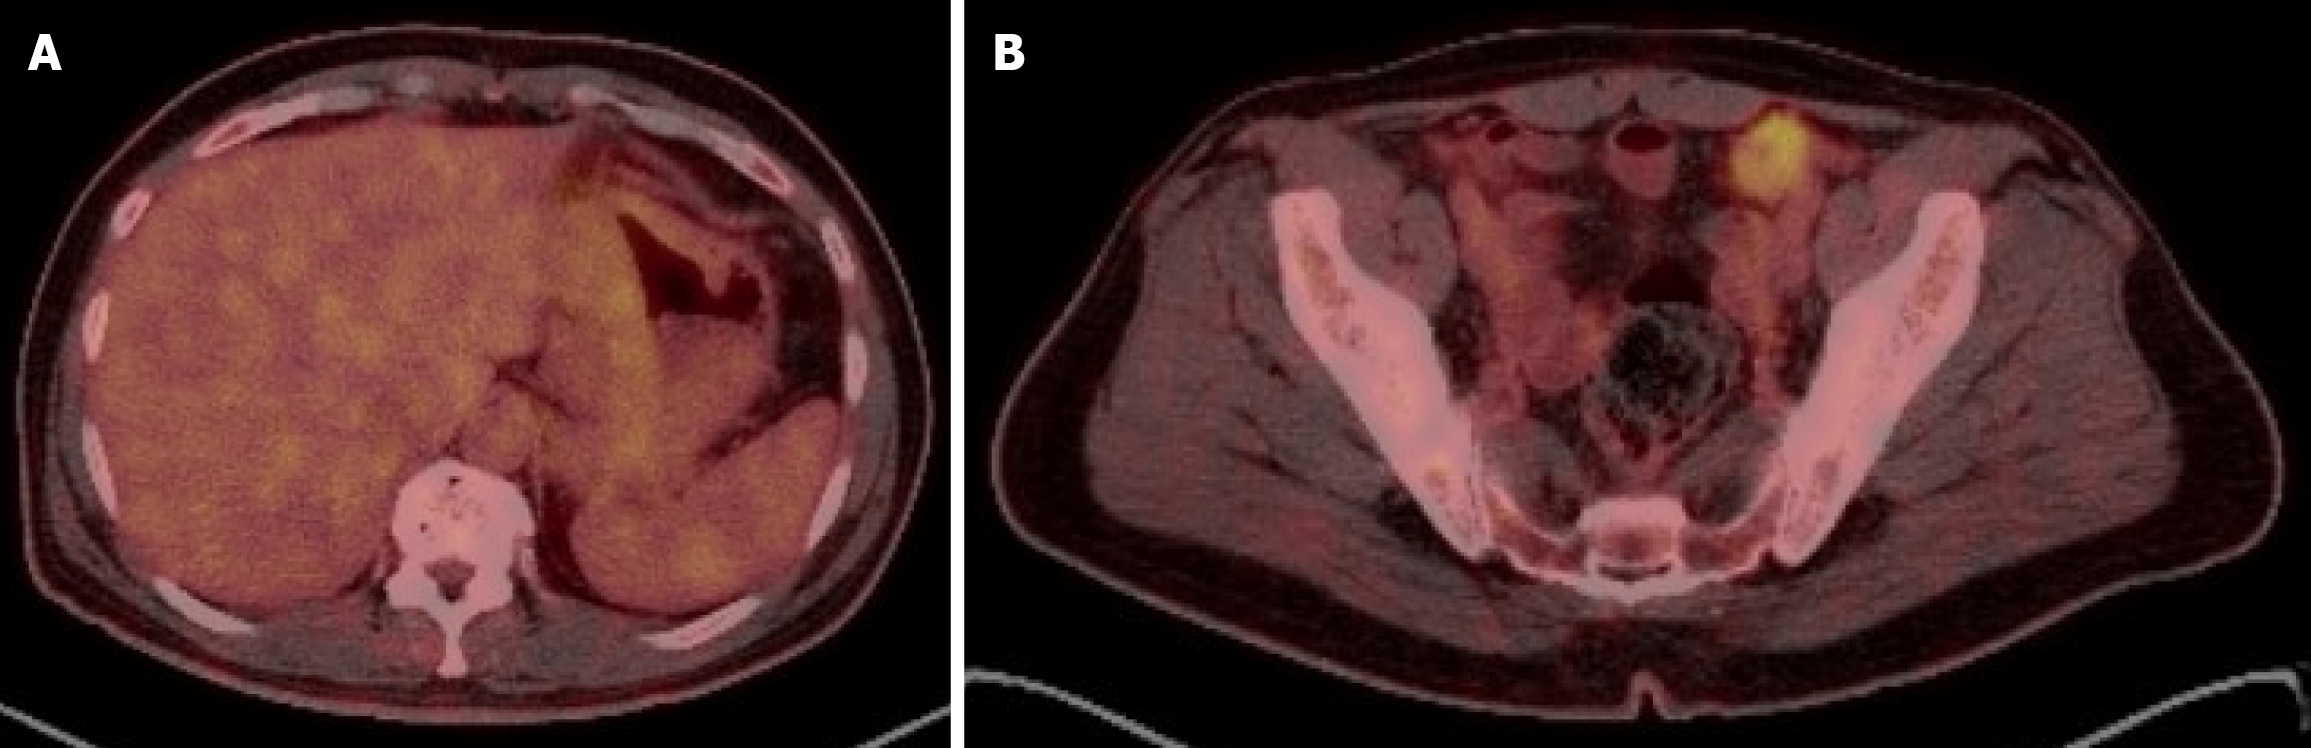

Figure 1 Initial radiological staging.

A: Computed tomography (CT) scan of the chest, abdomen and pelvis scan showing a mural thickening of the lesser curvature of stomach reaching the antrum, associated with locoregional lymphadenopathy; B: Whole positron emission tomography/CT scan showing FDG avid gastric thinking.